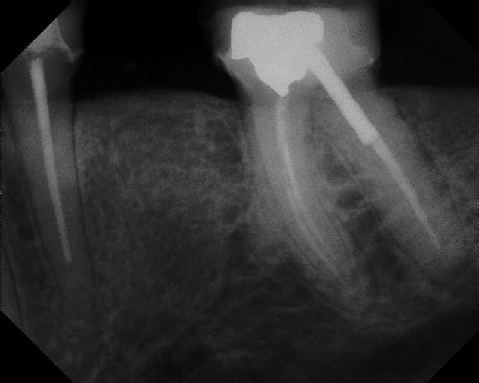

Pre-op Post-op 1 Post-op 2